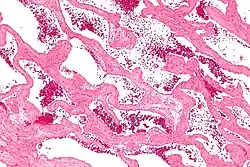

| Micrograph of a cavernous liver hemangioma. H&E stain. | |